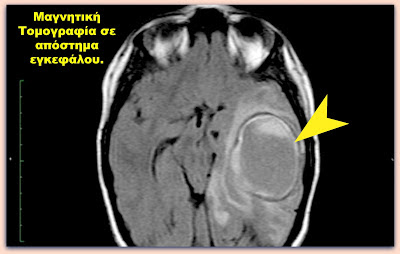

Το εγκεφαλικό απόστημα αποτελεί εστιακή πυώδη συλλογή μέσα στο εγκεφαλικό παρέγχυμα. Είναι συχνότερο στις 4 πρώτες δεκαετίες της ζωής του ανθρώπου, καθώς αυτή την περίοδο εμφανίζονται οι κυριότεροι προδιαθεσικοί παράγοντες για την ανάπτυξή του (ωτίτιδα, παραρρινοκολπίτιδα, κρανιοεγκεφαλική κάκωση, συγγενής καρδιοπάθεια). Τουλάχιστον στο 15% των περιπτώσεων δεν εντοπίζεται η αιτία που προκαλεί το εγκεφαλικό απόστημα. Η συχνότητα εμφάνισής του ποικίλλει ανάλογα με τη γεωγραφική περιοχή και τις συνθήκες διαβίωσης των ατόμων. Επιπλέον είναι συχνή σε ανοσοκατεσταλμένους ασθενείς, που είναι επιρρεπείς στις ευκαιριακές λοιμώξεις. Η θνητότητα της νόσου κυμαίνεται 5 – 30% και η έκβασή της επηρεάζεται από πολλούς παράγοντες, όπως ο αριθμός, η εντόπιση και η αιτιολογία του αποστήματος, καθώς και η ηλικία και η νευρολογική κατάσταση του ασθενούς, η ανάπτυξη επιπλοκών και η μικροβιολογία των αποστημάτων. Η μικροβιολογία των εγκεφαλικών αποστημάτων ποικίλλει. Στις περισσότερες περιπτώσεις είναι πολυμικροβιακά (30 – 60%) και περιλαμβάνουν βακτήρια, μύκητες και παράσιτα, με τους αναερόβιους στρεπτόκοκκους να εμφανίζονται σε μεγαλύτερη συχνότητα.